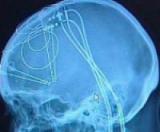

Стимуляция конкретных областей мозга приводит к образованию новых нейронов и улучшает память. Клиническая процедура, называемая глубокой стимуляцией мозга, посылает электрические импульсы по электродам...